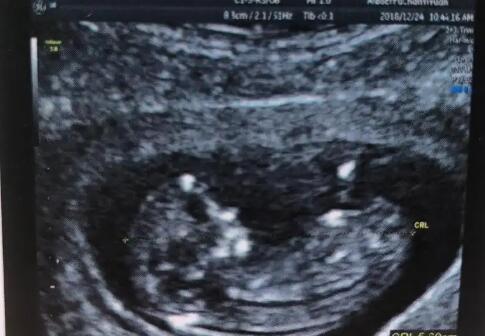

南宁市做试管婴儿的价格 2022年南宁可以包生男生试管医院分享 ‘彩超下的男孩